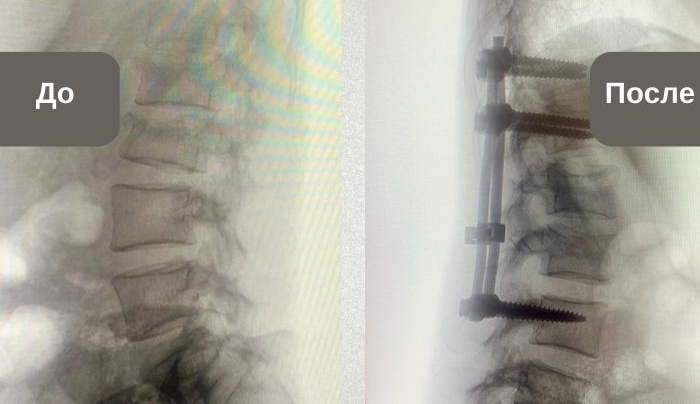

«Пациентка поступила с выраженным смещением двух позвонков. Потенциально это категория спинальных больных с парализацией после травмы. Шансы на сращение без операции были минимальны. Приняли решение женщину прооперировать. Произвели транспедикулярную фиксацию позвоночника – операцию для стабилизации позвонков при помощи имплантов из биосовместимых материалов, которые не отторгаются организмом», – пояснил заведующий отделением травматологии Михаил Черников.

Благодаря установке винтов позвоночник получает надежную опору и плотно фиксируется, не давая позвонкам смещаться в процессе заживления. Динамическая фиксация дает возможность пациенту двигаться без ограничений, не испытывая болевых ощущений. Но главное – обеспечивает правильное сращение перелома и помогает избежать негативных отдаленных последствий травмы.

Фото пресс-службы ГБ №3 Магнитогорска